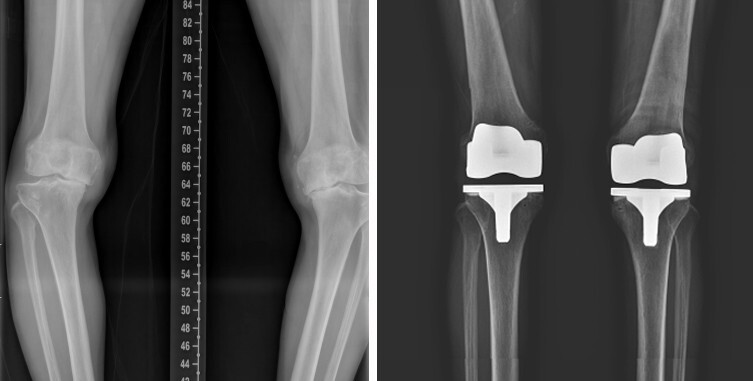

반면 연골 손상이 심해 일상생활이 어려운 경우에는 인공관절 수술이 필요하다. 안쪽 관절만 손상된 경우에는 인공관절 부분치환술을, 무릎 전체 관절의 퇴행이 심한 경우에는 인공관절 전 치환술을 시행한다. 부분치환술은 손상된 부위만 교체해 회복이 비교적 빠르다는 장점이 있으며, 전 치환술은 관절 전체를 교체해 통증을 근본적으로 해결하는 수술이다.

인공관절 치환술은 손상된 관절면을 정교하게 절삭한 뒤 금속 인공관절과 특수 삽입물을 삽입해 관절 기능을 회복시키는 방식으로 진행된다. 수술 후에는 통증 감소와 함께 다리 정렬이 교정돼 보행 기능이 개선된다. 다만 수술 결과를 좌우하는 것은 수술 이후의 재활이다.